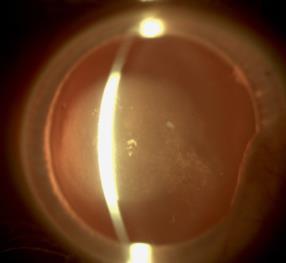

Off-label use of the Alcon Acrysof® IQ Vivity® EDOF IOL can give good uncorrected distance and intermediate visual acuity in non-pristine eyes with an epiretinal membrane, according to a study presented by Antti Viljanen, MD. The study evaluated visual acuity at different distances in patients with epiretinal membrane after a successful cataract surgery or refractive lens exchange surgery.

“Patients with non-pristine eyes want to have spectacle freedom,” he said.

The study was conducted in Turku, Finland with one single surgeon. It involved 17 eyes from 9 patients (5 male, 4 female) with a mean age of 63 years, an asymptomatic epiretinal membrane, and no reported distortion in preoperative check-up. Epiretinal membranes were found in 14 eyes through preoperative OCT imaging. Toric IOLs were used when applicable and micromonovision was targeted. A Barrett lens factor of 1.94 was used.

The first post-surgery visit was at one month and yearly afterward. Main outcome parameters were LogMAR uncorrected and corrected visual acuity at distance (UDVA 6 m), intermediate (binocular UIVA 63 and 100 cm) and near (binocular UCNVA 40 cm). ETDRS type charts with rulers were used.

The results were good—preoperative corrected visual acuities were logMar 0.00/0.04, right/left eye, with spherical refractive error range -3.0 - +2.9D/-6.8 - +3.3D, mean

near add was 2.2D, and mean implanted IOL power was 20.5D/21.3D. At one year, none of the patients had distance-corrected spectacles and 5 of 9 did not need reading glasses. Binocular UDVA was logMar 0.00. UDVA was logMar 0.05/0.12. CDVA was logMar 0.01/-0.01. Mean anisometropia was 0.26D. UCNVA at 40cm was logMar 0.32. UIVA was logMar 0.09 at 63cm and logMar 0.00 at 100cm. No halos or distortions were reported.

Dr Viljanen briefly presented the case of a patient who received her diagnosis four years before the implantation of the Vivity IOL lens, which occurred in 2020. Five years after the operation and presenting at every follow up, she has good vision and normal visual acuity and is not using glasses for reading because of the micromonovision.